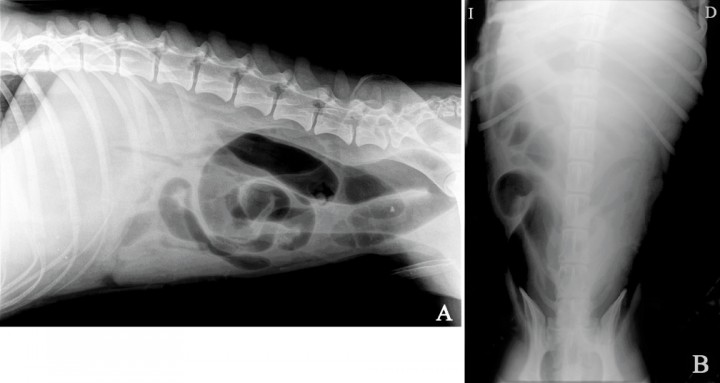

Se presenta en la consulta un perro proveniente de una protectora, macho, mestizo de 1 año y medio de edad, castrado y 35 kg de peso, con sintomatología de vómitos crónicos y adelgazamiento de dos semanas de evolución. En el examen físico se apreció una marcada deshidratación (7,5 %), taquicardia (120 lpm), mucosas congestivas, dolor abdominal y dos trayectos fistulosos con secreción purulenta en la pared abdominal ventral en el lado derecho del prepucio, compatibles con una herida por mordedura. En el análisis sanguíneo se observó una elevada leucocitosis de 32 x 109/L (valores de referencia: 6-17 x 109/L) e hipoalbuminemia de 1,9 g/dl (valores de referencia: 2,5-3,6 g/dl). Se realizó un examen radiográfico de la cavidad abdominal (Figs. 1A y B).

<p>Imagen radiográfica de la cavidad abdominal de un perro mestizo de un año y medio de edad, con historia clínica de vómitos crónicos y adelgazamiento de dos semanas de evolución. (<strong>A</strong>) Proyección lateral. (<strong>B</strong>) Proyección ventrodorsal.</p>

Imagen radiográfica de la cavidad abdominal de un perro mestizo de un año y medio de edad, con historia clínica de vómitos crónicos y adelgazamiento de dos semanas de evolución. (A) Proyección lateral. (B) Proyección ventrodorsal.